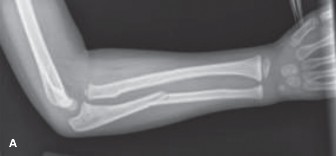

CASE 5 A 30-year-old male fell while he was out for a run. He landed awkwardly…